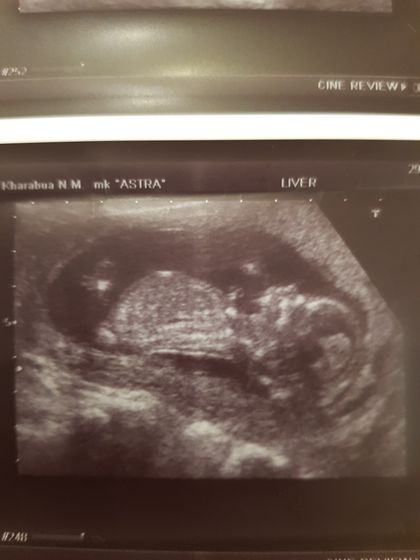

Была на первом скрининге. 14 неделек. Узист сказала пол, мне интересно, кто опытный, видно по фото какой именно пол? Я пересмотрела кучу фото и постов, ну никак не вижу ?

Я думаю, это мальчик?)

Это если бы вам фото сделали не человечка вашего, а фото между ножек, то было бы понятно, а так это типа на кого больше похоже на меня или на мужа )))

Самое интересное, что муж был на узи, и ракурса между ножек не было, только с боку, вот и подумалось, вдруг видно!)

По такому фото вам и узист не скажет. Там есть определённые параметры, развития половых органов по которым они говорят. Мне на 1м скрининге сказали верно.

Как с такого ракурса что-то увидеть?

Не думаю, что с этого ракурса узист разглядел

По такому фото не Сказать